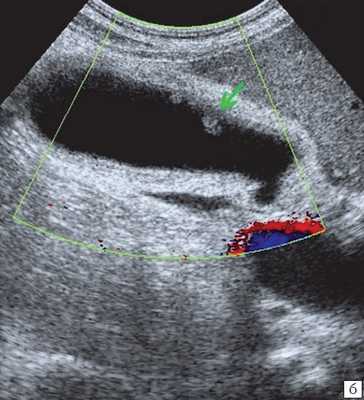

При распространенном холестерозе визуализируются множественные гиперэхогенные образования, дающие картину "земляничного" желчного пузыря (рис. 3).

а) Множественные полипы в желчном пузыре, картина "земляничного" желчного пузыря.

б) В режиме цветного допплеровского картирования кровоток не регистрируется.